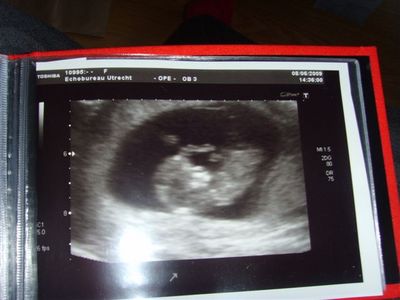

een wonder

2009-06-22

Liefde is een wonder een kind is klein en alles zit erop en eraan zie laatste foto's

Liefde is een wonder een kind een groter wonder